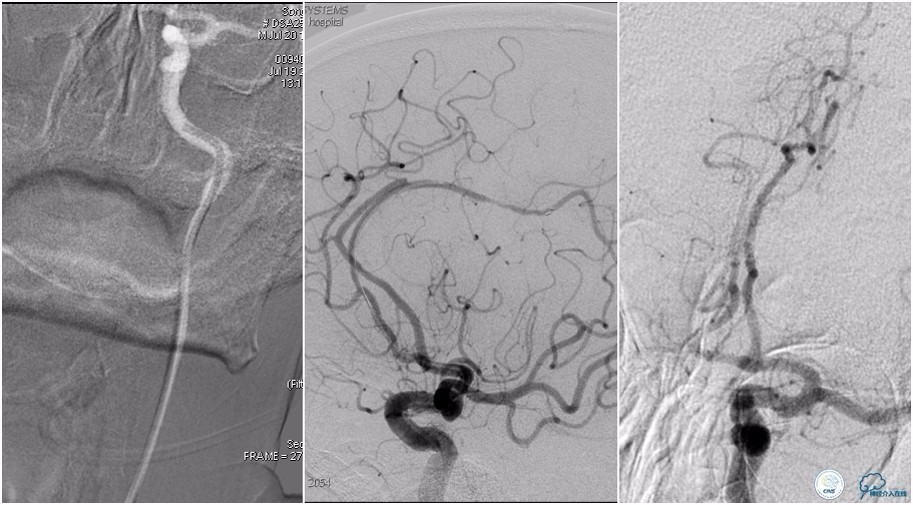

术后头颅CT复查。

术后复查头颅CTA。

术后复查头颅MRI。

术后第二天患者意识清,言语清,右上肢肌力1级,右下肢肌力3级,左上肢肌力5级,左下肢3级。

术后90天随访右上肢肌力3级,左上肢肌力5级,双下肢肌力4级,mRS评分3分。

3.该患者治疗过程中存在一定不够,患者右侧肢体偏瘫症状明显,取栓过程中因血管扭曲未能优先处理左侧大脑前动脉。虽然术后血流完全再通,但复查头颅MRI左侧大脑前供血区域仍有大片梗死,右侧上肢肌力恢复不理想。